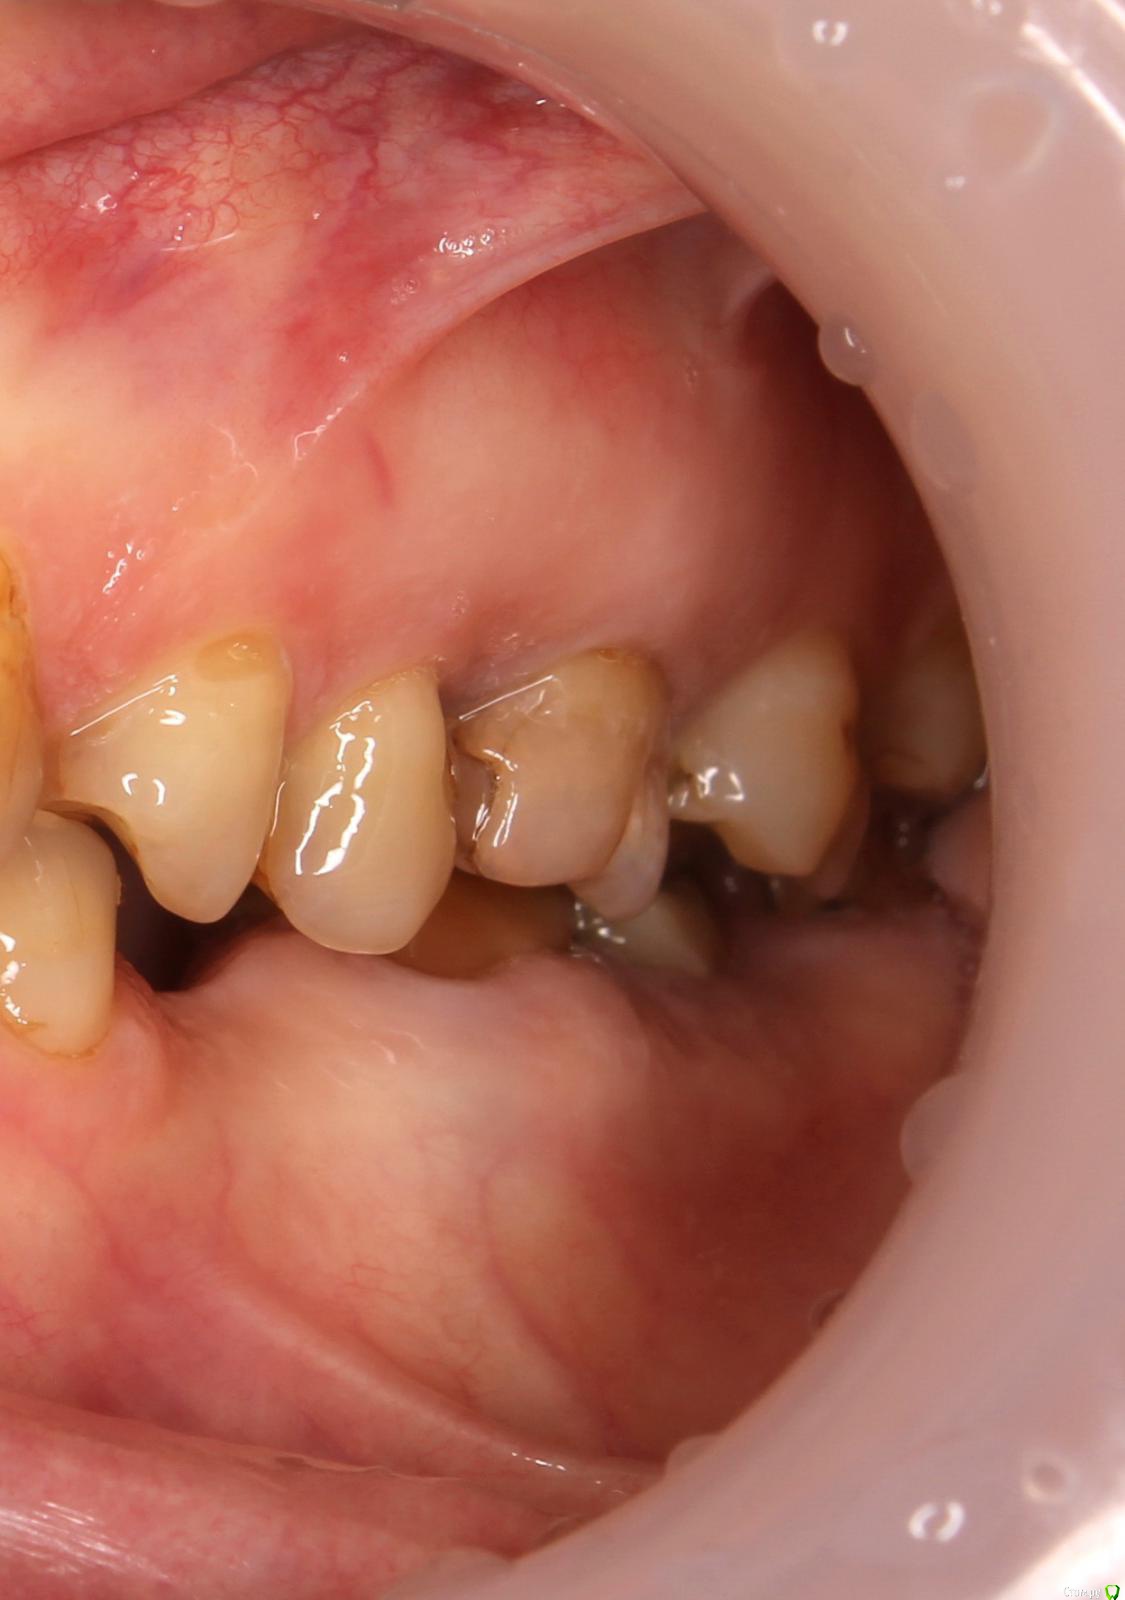

LOLga777 Опубликовано 24 ноября, 2019 Поделиться Опубликовано 24 ноября, 2019 (изменено) Здравствуйте, уважаемые врачи.37-й зуб. Депульпирован, стояла большая пломба. В 2013 году откололась наружная стенка зуба, скол близко к корню. Стоматологом № 1 был поставлен штифт, коронка восстановлена пломбой (фото с торчащим штифтом от 2013 года). Через год наружная часть пломбы откололась прямо по штифту, так ходила три года, ничего не царапало, не мешало. В 2016 году стоматолог № 2 в поликлинике уговорила запломбировать, в результате сделала скошенную наружную часть пломбы. Фото ротовой полости справа от 07.2019 г. прилагаю. Вопрос: что делать с 37-й зубом? Хирург не хочет удалять, говорит, что можно восстановить пломбой, и боится повредить 36-й. Не знаю, видно ли на снимках, в каком канале стоит штифт и можно ли поставить еще один штифт (второй штифт врач не поставила, насколько я помню, из-за того, что будет дороже и еще что-то там может не выдержать). Без второго штифта пломба, повторяющая анатомическую форму зуба, я считаю, простоит максимум год. С 36-м зубом тоже непонятно что делать, не идет ли там процесс кариеса на корне… Между корнями что-то черное (на КТ и 2016 года и 05.2019 года). Не хотелось бы покрывать коронкой зуб с гранулемой между корнями. Стоматолог предложил рассверлить пломбу и посмотреть.У меня ВОПРОС: можно ли будет что-то увидеть после рассверливания зуба, если процесс идет под «дном»? После сверления снимется еще часть тканей, а их там и так мало. По вкладкам и коронкам на 37-й зуб, наверное, надо продублировать тему в раздел «Протезирование». P.s. Есть большое количество других проблем Изменено 24 ноября, 2019 пользователем LOLga777 Ссылка на комментарий

LOLga777 Опубликовано 24 ноября, 2019 Автор Поделиться Опубликовано 24 ноября, 2019 (изменено) тогда идете к стоматологу ортопеду в этой клинике и берете направлениеЭто платно. Я заявление напишу, чтоб удалил. У меня очень сложная ситуация. Мне уже говорят о тотальном протезировании, но я пока как-то не готова. После несанкционированного вмешательства в 47-й зуб спилили небный бугор 17-го зуба и пришлифовали 18, 47, 48. Прикус снизился. После спиливания бугра мне стало не хватать высоты зубов. Рассказывать долго, что было еще. Сейчас щелчки в ВНЧС остались, хорошо, хоть рот стал открываться на 3 пальца. По хорошему, надо идти к гнатологу с МРТ и КТ. Без тотального протезирования я не знаю, как исправлять заглаженные поверхности зубов и искать окклюзию, мне не хватает спиленного бугра, сейчас уже не восстановить того, что было. 46-й зуб хирург тоже ранее отказался удалять. Терапевт при вскрытии обнаружил кусок инструмента в дистальном канале, извлечь не смог. Сейчас зуб закрыт временной пломбой, которая наполовину уже разрушилась.Теперь думаю, какой зуб удалять - 37 или 46. Левой стороной (фото с тремя зубами) не очень пожуешь, но и с открытым 46-м долго нельзя ходить... А кто делает коронки в артикуляторе, разве хирург-имплантолог? Почему-то не прикрепляется снимок 46-го зуба с инструментом Изменено 24 ноября, 2019 пользователем LOLga777 Ссылка на комментарий